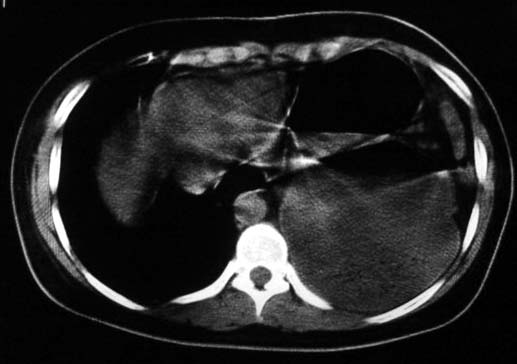

标题: CT5517:女性、24岁,反复胸痛、气促不能平卧半月。 [打印本页]

标题: CT5517:女性、24岁,反复胸痛、气促不能平卧半月。

左肺可见二个含气或液气的囊状影,左肺段支气管、左肺动脉显示不清,纵隔右移,考虑:左肺支气管肺囊肿,左肺发育不良,纵隔疝。

左侧气液腔与胃腔影相连,考虑膈疝。钡餐检查有助于诊断。

我看这是膈疝,在纵隔窗第六\\七幅图像上可见胃粘膜影,再者可见两个腔影,这在液气胸是不会有的.

支持膈疝,纵隔窗内可见消化道的内容物。

液气胸 怎么会有2 个大腔?

左肺发育不良、支气管囊肿 应该纵隔左移的多吧

还是个膈疝